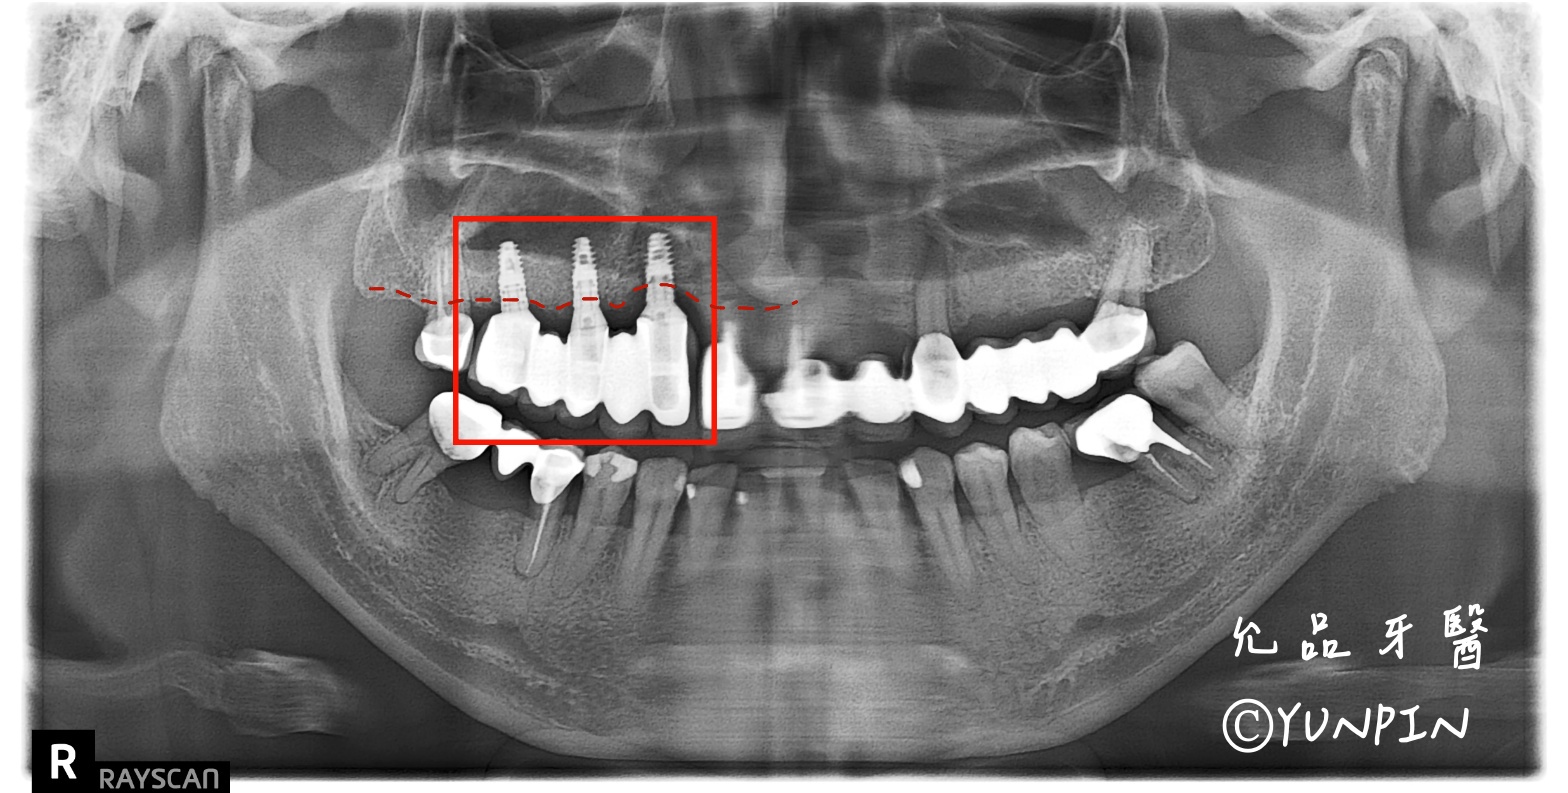

植體周圍炎導致周遭骨頭遭到破壞嚴重植體無法保留,